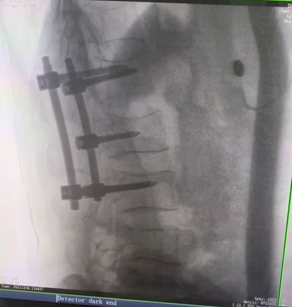

例如治療先天性脊柱側(cè)后凸畸形,由于脊柱自身復(fù)雜的解剖結(jié)構(gòu)限制,使得脊柱外科手術(shù)對(duì)于準(zhǔn)確度有著較高要求。以往我們只能采用傳統(tǒng)的正側(cè)位圖像來(lái)判斷螺釘置入的位置,現(xiàn)在三維C形臂特有的類CT斷層成像,使得治療過(guò)程可視化,立體化,在術(shù)中非常直觀地判斷螺釘植入的準(zhǔn)確度??捎行б龑?dǎo)術(shù)者植入后路螺釘并切除半錐體。同時(shí)可以在術(shù)中實(shí)時(shí)驗(yàn)證手術(shù)效果。有效地縮短了手術(shù)時(shí)間,降低手術(shù)風(fēng)險(xiǎn),避免了不必要的術(shù)后翻修手術(shù)。